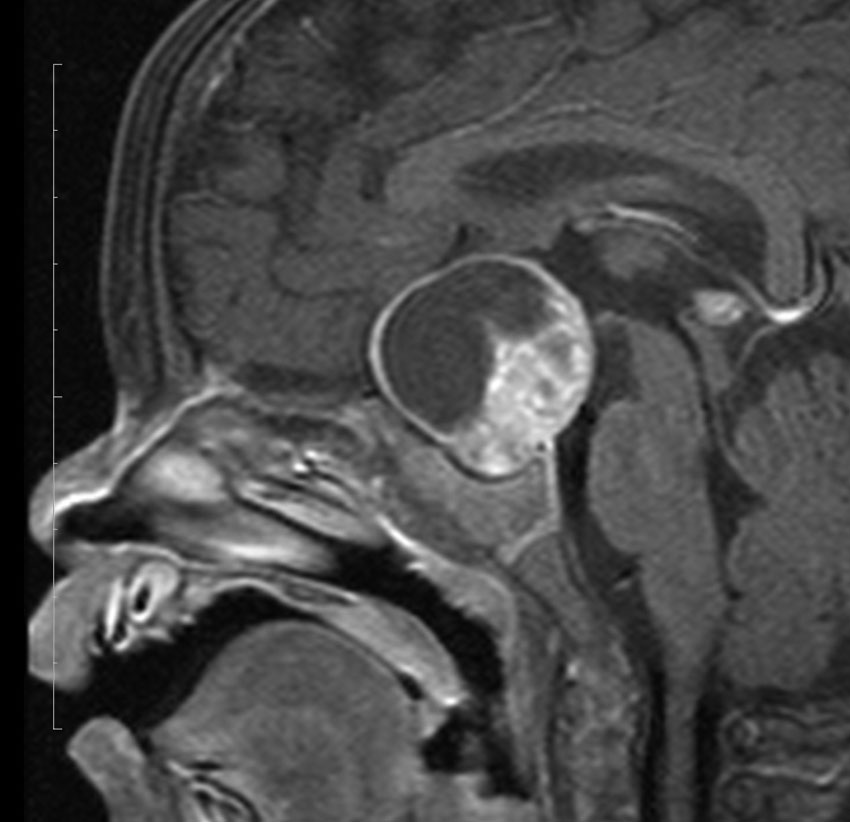

ちょっと大きな頭蓋咽頭腫です

嚢胞(液体が入っている袋)の部分と,腫瘍細胞が固まっている実質部分が入り交じっています。このくらいの大きさになってしまうと,下垂体機能を残すことはとても難しくなります。視神経が圧迫されて視力低下と視野障害を生じます。第3脳室が腫瘍で閉塞していて水頭症になっていますから知能の活動が低下します。

腫瘍を摘出するのに危ないのは,脳の血管の損傷です。左では白く,右では黒く線状に移っているのが太い脳動脈です。これら以外にもたくさんの細い重要な動脈が絡んでいます。

幸いこの患者さんの腫瘍は摘出できて患者さんは元気になりました。でもこのくらいのサイズになると手術がいつもうまくいくとは限りませんし重大な障害が残ることもあります。